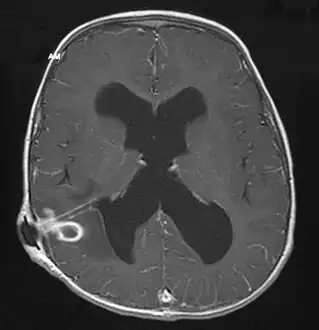

| Brain abscess in a person with a CSF shunt.[1] | |

MRI (T1 with contrast) showing the ring-enhancing lesion. From a rare case report of an abscess formed as a complication of the CSF shunt. Jamjoom et al., 2009.[1]

The diagnosis is established by a computed tomography (CT) (with contrast) examination. At the initial phase of the inflammation (which is referred to as cerebritis), the immature lesion does not have a capsule and it may be difficult to distinguish it from other space-occupying lesions or infarcts of the brain. Within 4–5 days the inflammation and the concomitant dead brain tissue are surrounded with a capsule, which gives the lesion the famous ring-enhancing lesion appearance on CT examination with contrast (since intravenously applied contrast material can not pass through the capsule, it is collected around the lesion and looks as a ring surrounding the relatively dark lesion). Lumbar puncture procedure, which is performed in many infectious disorders of the central nervous system is contraindicated in this condition (as it is in all space-occupying lesions of the brain) because removing a certain portion of the cerebrospinal fluid may alter the concrete intracranial pressure balances and causes the brain tissue to move across structures within the skull (brain herniation).

Ring enhancement may also be observed in cerebral hemorrhages (bleeding) and some brain tumors. However, in the presence of the rapidly progressive course with fever, focal neurologic findings (hemiparesis, aphasia etc.) and signs of increased intracranial pressure, the most likely diagnosis should be the brain abscess.